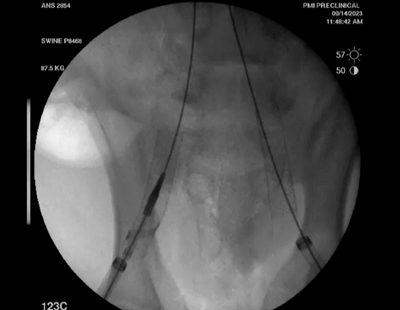

Recana支架內(nèi)旋切